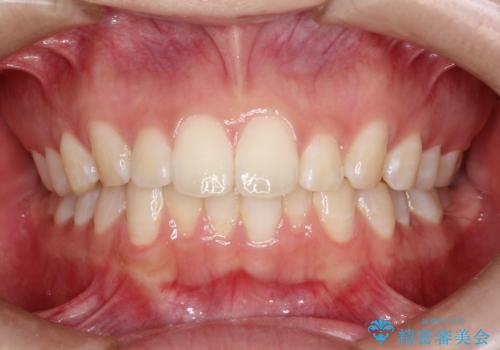

口元を下げてすっきりさせたい ワイヤー抜歯矯正で口元の改善

前歯をしっかり下げることで、口元がすっきりしました。